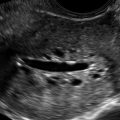

Figure E2-6 Endometrium of a 75-year-old asymptomatic woman who was on unopposed estrogen for more than 10 years. Despite the absence of bleeding, this endometrium of 8 mm was considered heterogeneous and abnormal, prompting sampling. Stage Ib endometrial carcinoma was diagnosed, invading one third of the way through the myometrium (invasion not detectable sonographically).